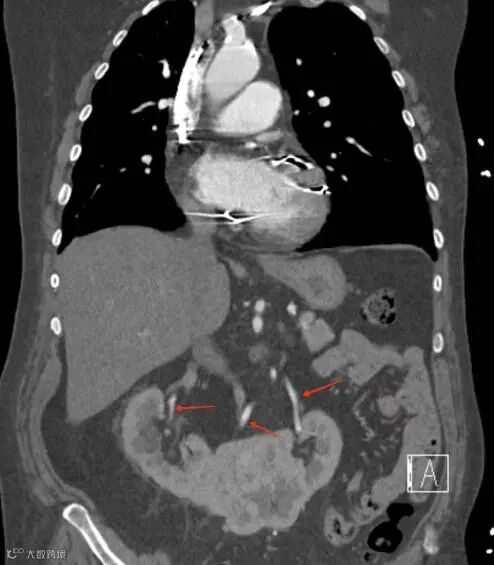

患者,男,60岁,因怀疑主动脉夹层而进行CTA检查,发现马蹄肾,肾峡部可见功能性肾实质,由三条肾动脉供血(箭头)。

马蹄肾合并左侧下腔静脉。双肾下极融合,双侧肾盂旁多发囊肿,下腔静脉(IVC)在肠系膜上动脉(SMA)起始部走形于主动脉左侧。